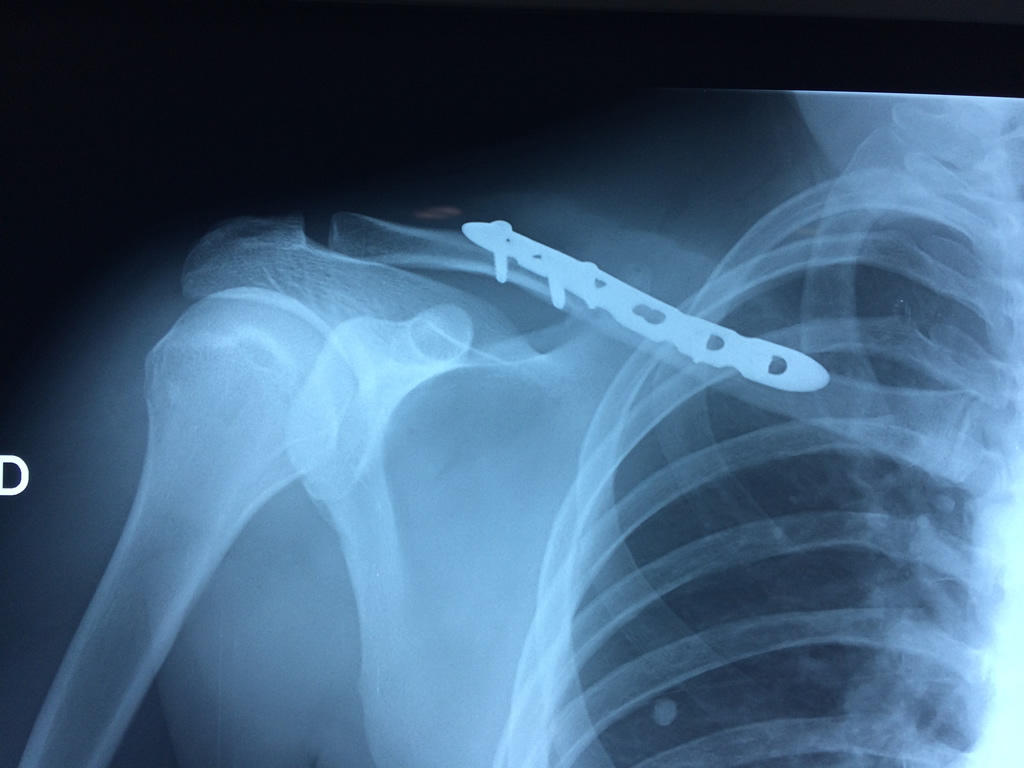

Fémur - Clavícula

La clavícula es un hueso largo, con forma de "S" itálica, situado en la parte anterosuperior del tórax. Junto con la escápula forman la cintura escapular. Se puede palpar por toda su longitud y se extiende del esternón al acromion de la escápula, siguiendo una dirección oblicua lateral y posterior.